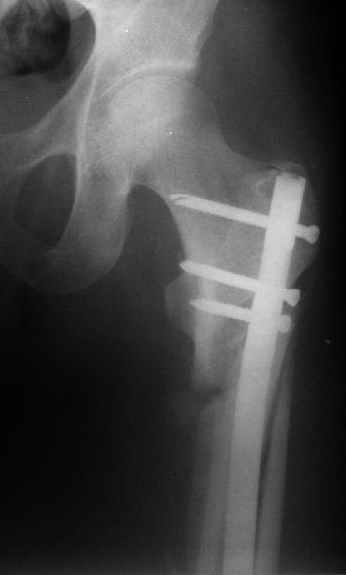

Могу скромно напомнить о существовании стержня нашей модификации.

В частности, на проксимальном конце сделано еще одно дополнительное статическое отверстие. Можно ввести в проксимальном отделе 4 винта, из них 3 статические (2 в круглые отверстия и 1 по нижнему краю овального). Картинки в приложении. На дистальном конце стержня тоже кое-что улучшено. Спрашивайте в аптеках, как говорится. Выпускается предприятием "ЦИТО" (Москва), то есть это малобюджетное решение.

Это было года 2,5 назад, мы тогда еще уточняли возможности шинирования с угловой стабильностью гвоздем с поперечным расположением винтов при переломах проксимального отдела бедра. Пациенту не пришлось приобретать намного более дорогой рекон или проксимальный гвоздь. В приложении еще несколько примеров применения того гвоздя при высоких переломах бедра, в том числе с более латеральной точкой входа. Гвоздь изгибаем для этого.